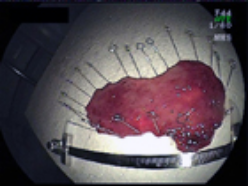

3.病変を取り去ったあとの胃と切除標本。胃の出口付近の粘膜のほとんどを剥離しました。

3.病変を取り去った後の直腸と切除標本。病変部の大きさはφ8cmでした。